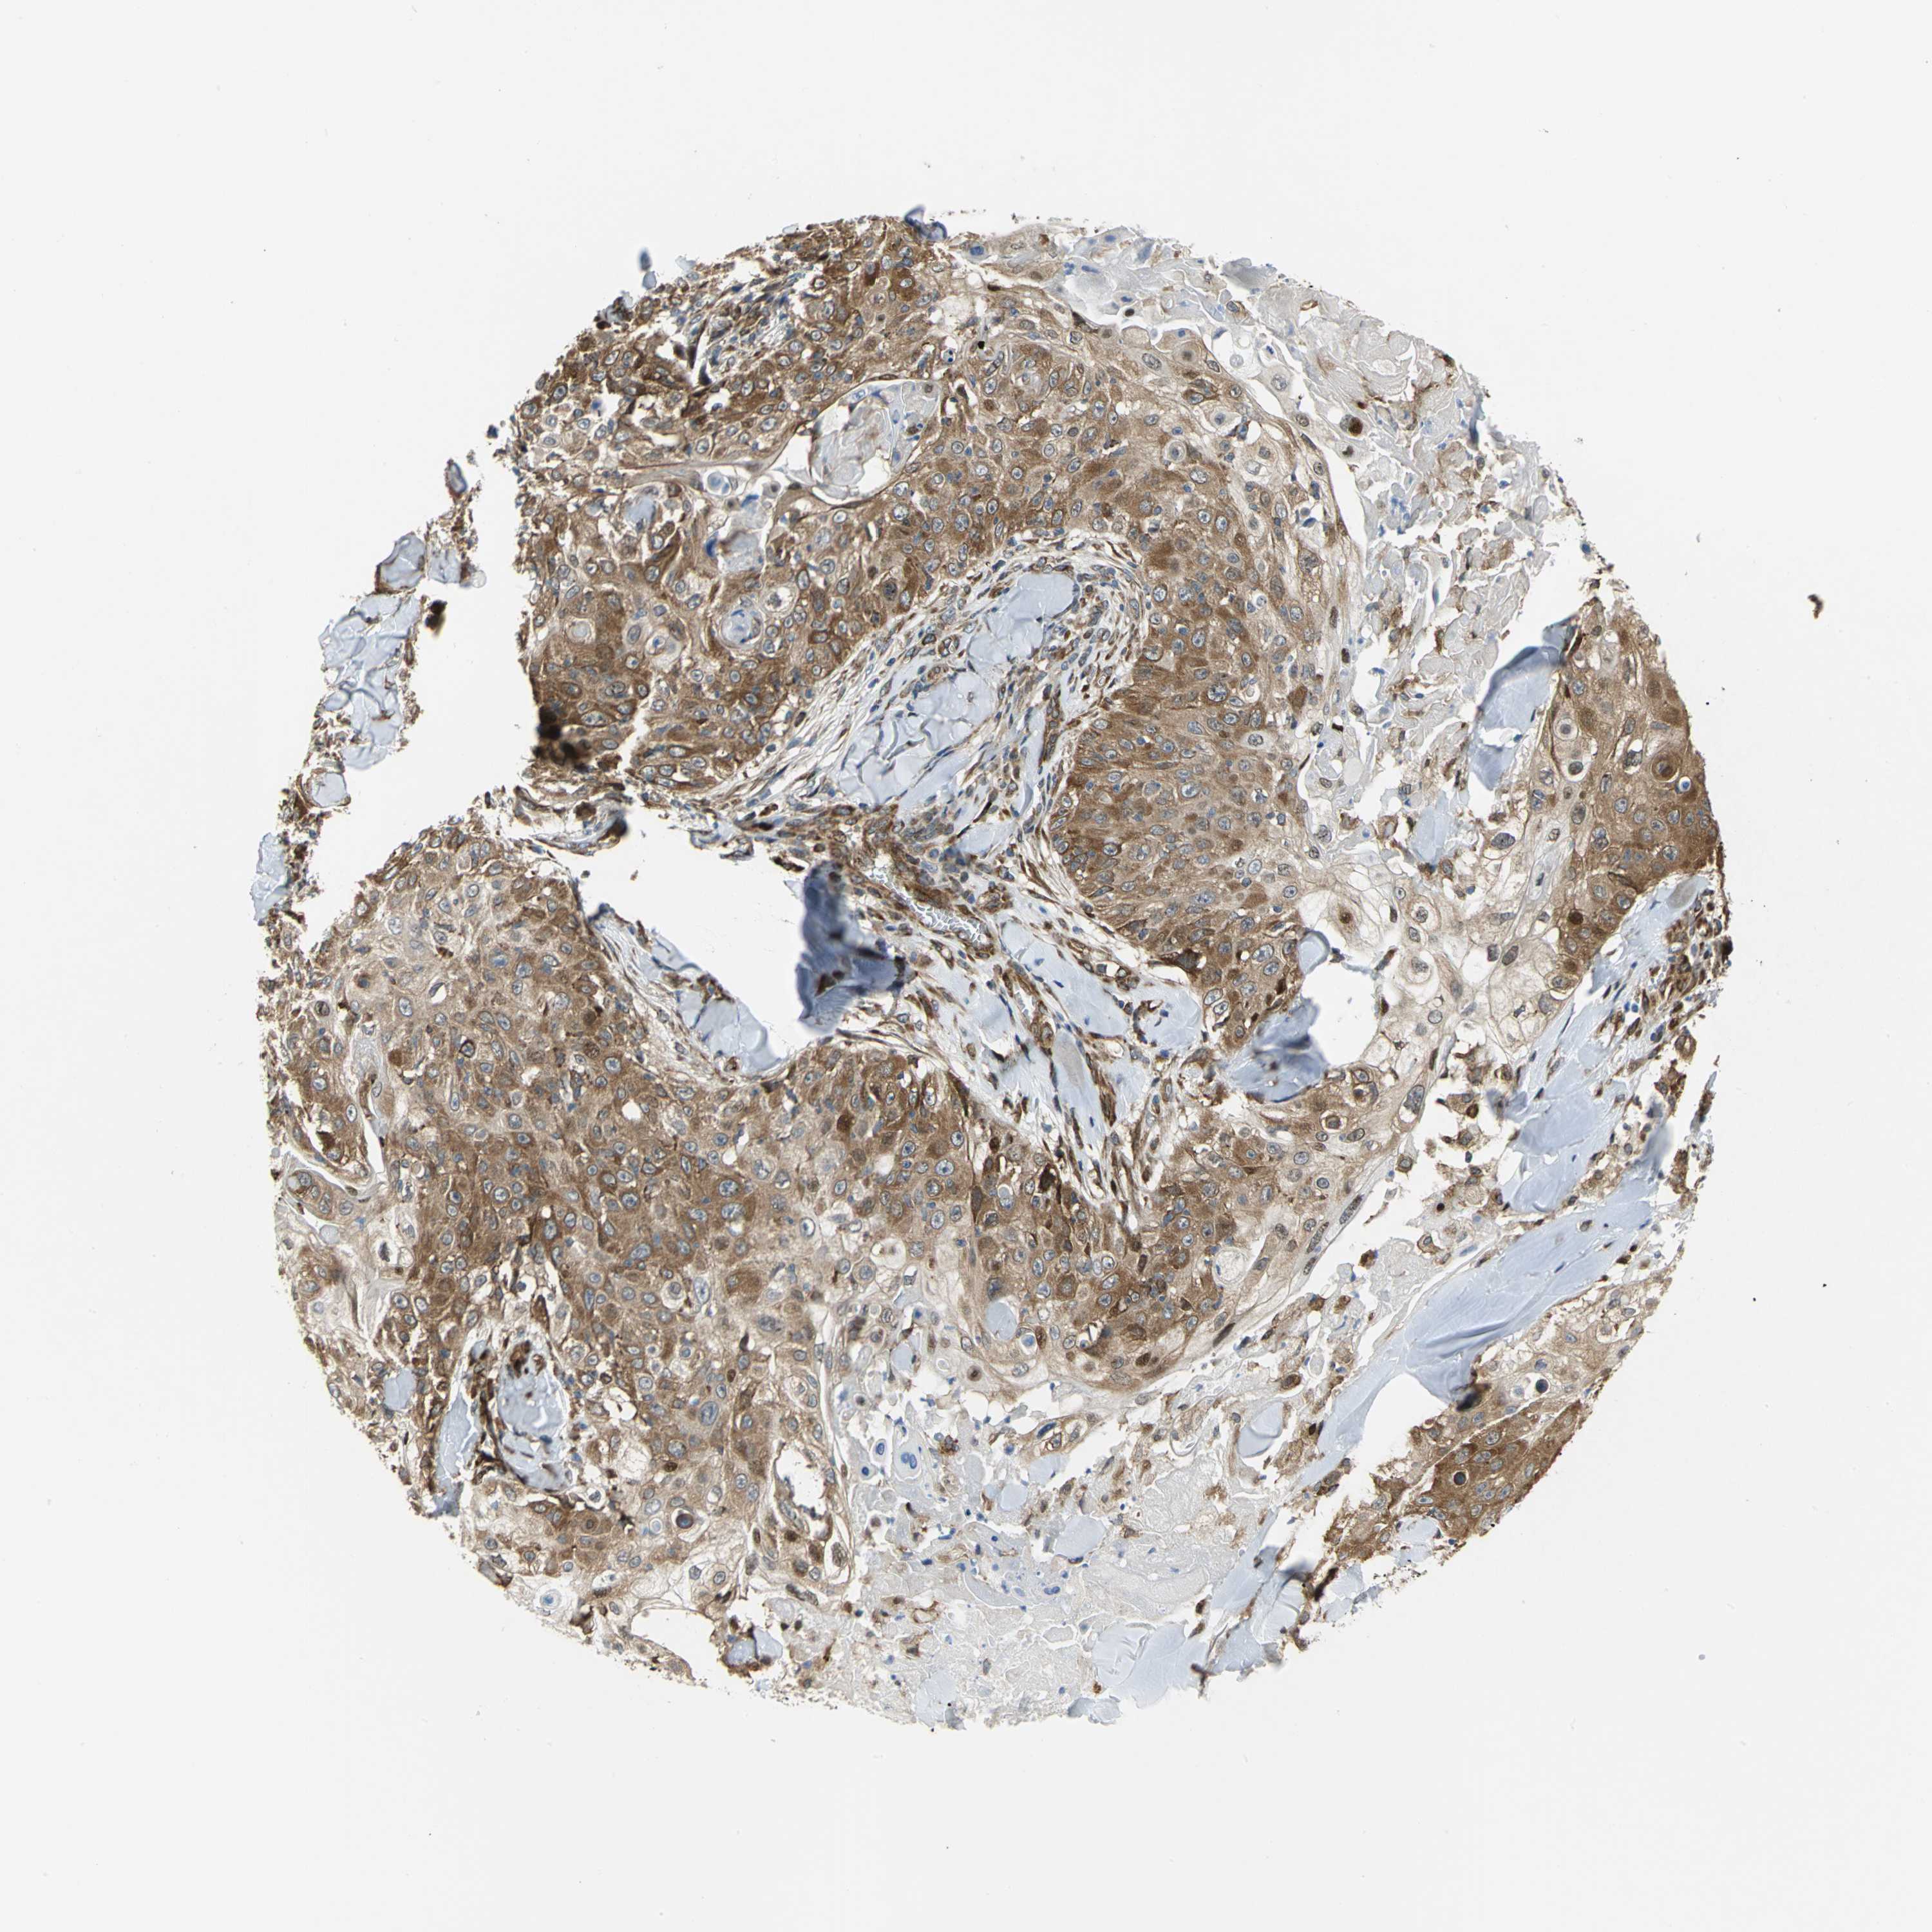

Basal cell and squamous cell cancer

SKIN CANCER - Protein expressioni

A mouse-over function shows sample information and annotation data. Click on an image to view it in a full screen mode. Samples can be filtered based on level of antibody staining by selecting one or several of the following categories: high, medium, low and not detected. The assay and annotation is described here.

Antibody stainingi

Antibody staining in the annotated cell types in the current human tissue is reported as not detected, low, medium, or high, based on conventional immunohistochemistry profiling in selected tissues. This score is based on the combination of the staining intensity and fraction of stained cells.

Each image is clickable and will lead to virtual microscopy that enables deeper exploration of all samples and also displays staining intensity scores, fraction scores and subcellular localization as well as patient and tissue information for each sample.

Antibody HPA057159

Staining

High

Medium

Low

Not detected

Intensity

Strong

Moderate

Weak

Negative

Quantity

>75%

75%-25%

<25%

None

Location

Nuclear

Cytoplasmic/membranous

Cytoplasmic/membranous,nuclear

Squamous cell carcinoma, NOS

Squamous cell carcinoma, metastatic, NOS